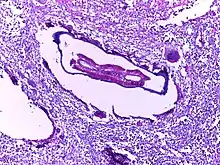

![]() | Helminth in appendix | Micrograph showing lumen of appendix and cut section of pin worm. | Category: Histopathology of appendix with Enterobius vermicularis | Parasitic helminthiasis infectious disease |